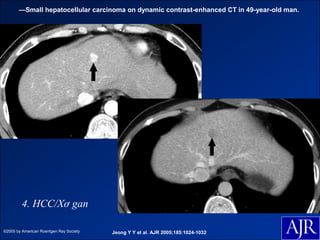

—Small hepatocellular carcinoma on dynamic contrast-enhanced CT in 49-year-old man.

4. HCC/Xơ gan

©2005 by American Roentgen Ray Society   Jeong Y Y et al. AJR 2005;185:1024-1032